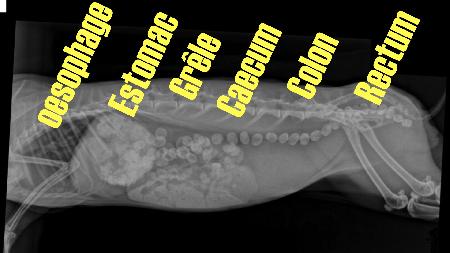

Dans cette partie, on va se concentrer sur la digestion au sens large,qui va de la préhension des aliments

Les Dents, la bouche, le pharynx

et toute la transformation qui va jusqu'Ã l'aboutissement,

Oesophage, Estomac, intestin grèle, Gros intestin, Caecum, Rectum, Anus.